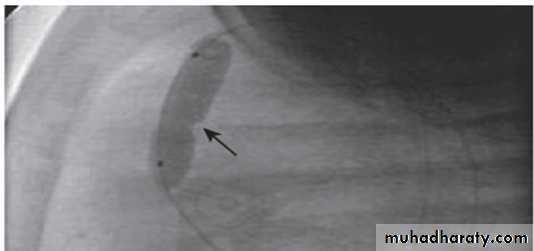

Valvar PS and balloon valvuloplasty

Inflation of the balloon catheter showing the indentation (arrow) made on the balloon from the stenotic valve.